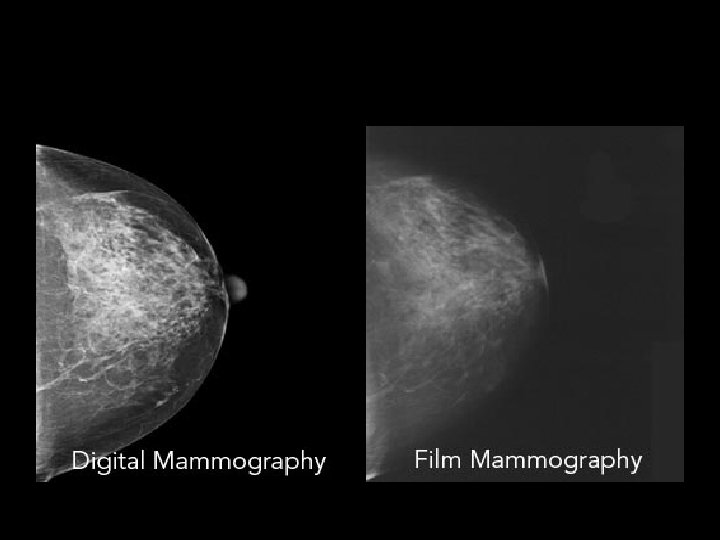

MAMMOGRAPHY Dawn Charman, RT (M) RADIOGRAPHIC IMAGING OF THE BREAST Diagnostic for breast cancer 34